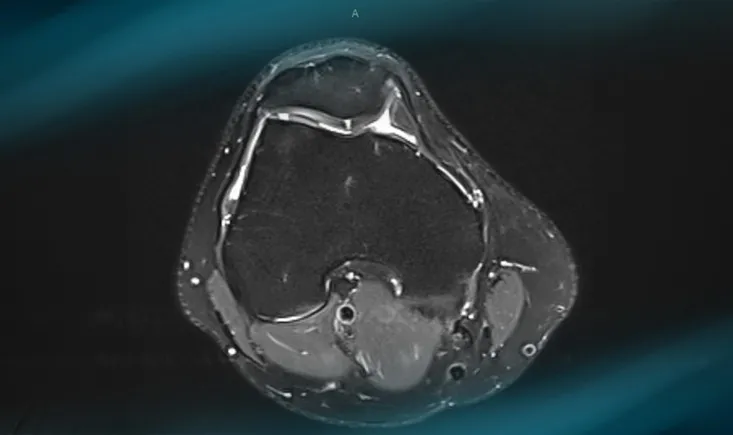

A 68-year-old woman has been suffering from mechanical bilateral knee pain for the past 6 years. The x-rays re…